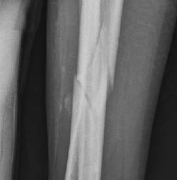

Tibial shaft fractures extending into the distal metaphysis and the tibial plafond represent a formidable challenge in orthopedic trauma. Historically, these complex injury patterns—often classified as AO/OTA 43-B or C, or 42 with distal extension—were managed primarily with plate osteosynthesis due to concerns regarding articular congruity and the inability of early generation intramedullary nails to secure short distal segments. However, the evolution of intramedullary nailing systems, featuring multi-planar distal locking options and advanced insertion trajectories, has revolutionized the management of these fractures.

Image

The epidemiology of these injuries demonstrates a bimodal distribution. High-energy trauma, such as motor vehicle collisions and falls from height, typically afflicts younger patients and presents with significant soft tissue compromise, comminution, and complex articular involvement. Conversely, low-energy torsional mechanisms are more frequently observed in the elderly population, often resulting in spiral fracture patterns that propagate into the joint.